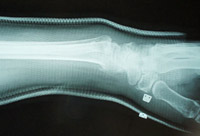

骨折(前腕骨遠位端部骨折の治療)

前腕骨遠位端部骨折の整復・固定

徒手整復で解剖学的整復位が得られています。

最も疼痛とリスクの少ないゼロ・ポジション法で整復しています。

固定は日常生活がしやすい内旋位固定を採用しています。